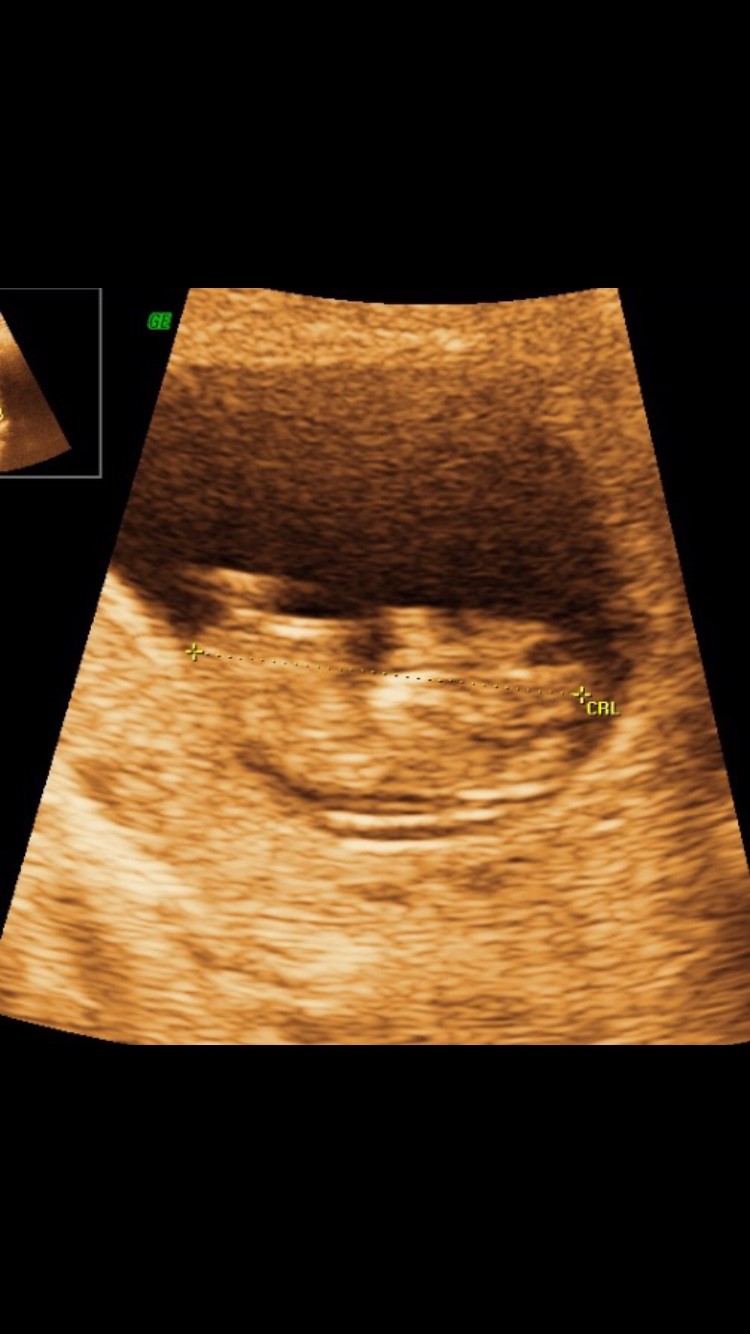

Når du har set hjerteblink så sent i 1. trimester, så er risikoen for at fosteret er dødt inden nf skanningen meget lille, måske det kan give lidt ro?

Jeg tror de fleste af os er nervøse,når det kommer til skanningerne, jeg er i hvert fald. Jeg er 10+4 og skal til nf om 18 dage. Og ja jeg er også nervøs. Trods massiv kvalme.